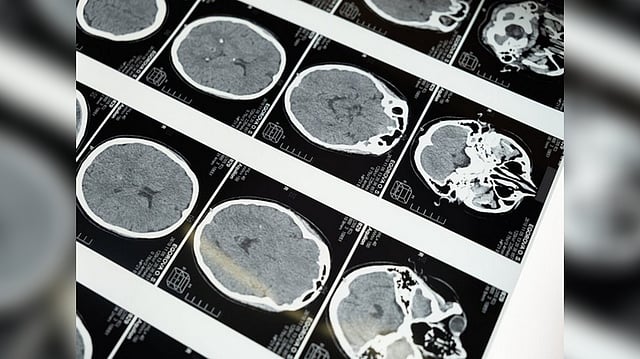

Study reveals how Huntington's disease affects different neurons

Neuroscientists at MIT have now shown that two distinct cell populations in the striatum are affected differently by Huntington's disease.

CAMBRIDGE: Neurons in the striatum, a part of the brain affected by Huntington's disease, are among the most severely affected. The degeneration of these neurons contributes to patients' loss of motor control, which is one of the disease's major symptoms.

Neuroscientists at MIT have now shown that two distinct cell populations in the striatum are affected differently by Huntington's disease. They believe that neurodegeneration of one of these populations leads to motor impairments, while damage to the other population, located in structures called striosomes, may account for the mood disorders that are often see in the early stages of the disease.